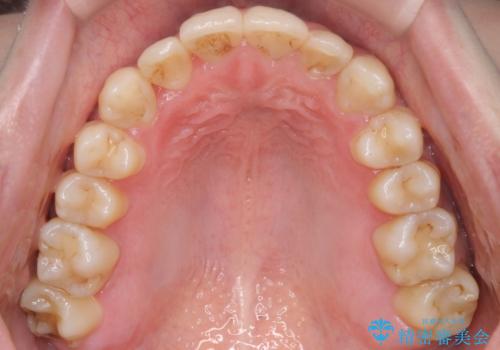

奥歯を後方に移動することで、歯を抜かずに矯正を終えることができました。